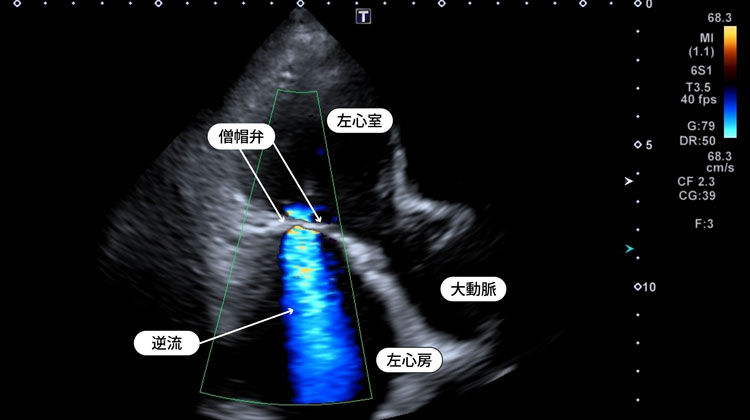

■僧帽弁逆流

心臓サイズの計測をしたり、心臓がどの程度動いているか、弁の逆流や通過障害が起こっていないかを調べる検査です。心筋梗塞では心臓の動きが特徴的に悪くなります。心筋梗塞を疑う症状が出たときには、すぐに心臓の動きを確認することは重要です。心臓には四つの部屋があり、逆流を防止するために四つの弁があります。この弁が閉まらなかったり、開きにくくなると息切れや失神などが起こることがあります。

また、心臓は肺と全身に血液を送り出すポンプですので、心臓の機能が落ちると肺や全身に水分(血液)が溜まり、むくみや息切れを起こすことがあります。これらに対しエコーは低侵襲に、リアルタイムで心臓の動きや機能を見ることができる唯一の画像検査です。健診や手術前の心機能評価で、偶発的に心房中隔欠損など先天性疾患を見つける場合もあり、身近に行われている検査でもあります。